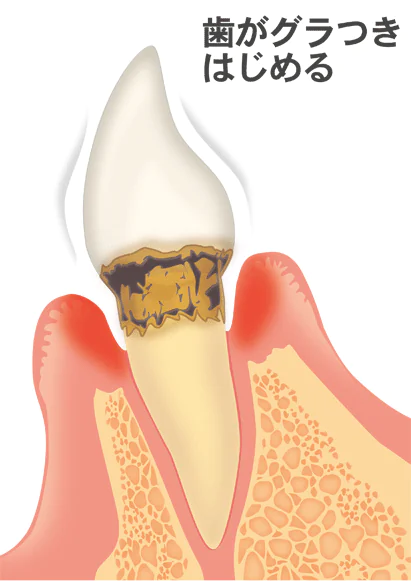

中度歯周病

中度歯周病では、歯槽骨が歯根の長さの3分の1~2分の1まで消失しています。炎症が悪化し、歯根部が露出し、歯に冷たいものや熱いものがしみます。歯石が付着し、口臭もひどくなります。